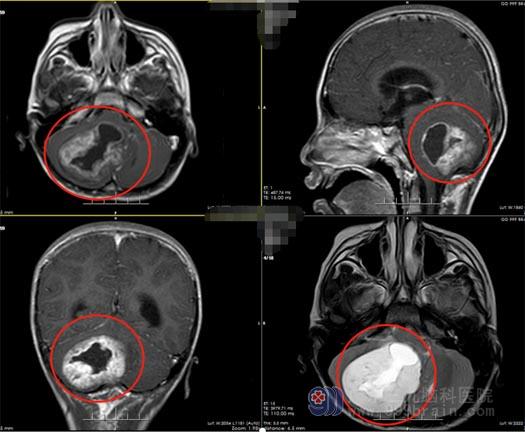

今年刚过完年,小文就开始出现呕吐。开始时,家里人以为过年吃的东西太杂,消化不良导致的,觉得养养胃就好了,没想到这一养就是半个月,症状没有丝毫的好转反而还有加重的趋势,这才让家人意识到了问题的严重性,在当地医院进行检查,头颅CT提示右侧小脑占位并脑积水,并且医生告诉他们小文的病情很严重,需要立即进行开颅手术,但是由于当地医疗技术水平有限,根本完成不了这个复杂的手术,一家人感觉天都要塌下来了。医生建议他们去广东三九脑科医院神经外五科看看,脑专科医院对这类颅脑肿瘤的疾病有着丰富的治疗经验,小文一家人像抓住了最后一根救命稻草,马不停蹄地赶往广州。

广东三九脑科医院鲁明副院长了解完小文的情况后也意识到事情不简单,立即安排小文进行了详细的检查,王国良主任带领外五科的专家团队进行了讨论,最后一致认为手术是最佳治疗方案,而且达到了刻不容缓的地步。在得到家属同意后,给小文实施了右侧小脑占位切除术,显微镜下全切肿瘤,手术顺利结束。

▲术前